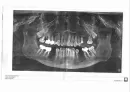

Мне 58 лет, собралась ставить импланты. Понимаю, что это дорогое удовольствие, но все же хочется понять корректность стоимости.

К отсутствующим трем зубам необходимо удалить еще 4 зуба. Еще мне нужно расщепить десну снизу под один имплант с каждой стороны. Согласна, зубы удалены давно. Стоимость операции по расщеплению 27000 руб.*2 и стоимость материала BIO GIDE 19000 руб.*2. Импланты Nobel TiUltra. Еще установка индивидуальных абатментов по 10000 руб. каждый.